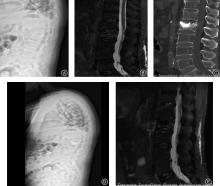

Objective To analyze the influencing factors for adjacent vertebral compression fractures (AVCF) after percutaneous kyphoplasty (PKP) in patients with osteoporotic vertebral compression fractures (OVCF), taking into account the sagittal parameters of the spine-pelvis, fracture characteristics, and treatment-related clinical features. Methods The research subjects were selected from OVCF patients admitted to the hospital between November 2020 and August 2023. A total of 240 cases were included, and their clinical data were retrospectively analyzed. All the patients underwent PKP surgery and were followed up for 2 years. Based on whether the selected patients experienced AVCF during the follow-up period, they were divided into the occurrence group (54 cases) and the non-occurrence group (186 cases). The clinical data and spinal pelvic sagittal plane parameters of the two groups were compared, and the risk factors were analyzed by multivariate Logistic regression analysis. The predictive value of the regression equation was analyzed by receiver operating characteristic (ROC) curves. Results The proportions of patients with diabetes, Ⅱ/Ⅲ degree fracture compression, initial fracture site T10-L2, bone cement intervertebral disc leakage, multi-segment fracture, and intervertebral disc injury in the occurrence group were 53.70%, 62.96%, 72.22%, 40.74%, 44.44%, and 33.33%, respectively, which were higher than those of 24.19%, 47.31%, 45.70%, 13.44%, 19.35%, and 13.98% in the non-occurrence group. The recovery rate of vertebral body height was lower than that in the non-occurrence group, and the TK, SVA, and TPA were higher than those in the non-occurrence group (P < 0.05). Diabetes (OR = 2.408), Ⅱ/Ⅲ degree fracture compression (OR = 2.838), bone cement disc leakage (OR = 1.547), multi-level fracture (OR = 2.155), disc injury (OR = 3.043), elevated TK (OR = 2.081), elevated SVA (OR = 2.298), and elevated TPA (OR = 1.636) were independent risk factors for AVCF in OVCF patients after PKP (P < 0.05). The increased vertebral height recovery rate (OR = 0.328) was an independent protective factor (P < 0.05). A regression equation was constructed: logit (P) = -7.087 + diabetes × 0.879 + fracture compression degree × 1.043 + bone cement intervertebral disc leakage × 0.436 + multi-level fracture × 0.768 + intervertebral disc injury × 1.113 - vertebral height recovery rate × 1.114 + TK × 0.733 + SVA × 0.832 + TPA × 0.436. The construction of the Logistic multiple regression diagnostic regression equation is effective. The ROC curve shows that when logit (P) > 0.174, the area under the curve (AUC) value is 0.898, and the diagnostic sensitivity and specificity are 83.33% and 82.80%, respectively. Conclusions Diabetes, Ⅱ/Ⅲ degree fracture compression, bone cement disc leakage, multi-level fracture, disc injury, elevated TK, elevated SVA, and elevated TPA were identified as independent risk factors for AVCF in OVCF patients after PKP, the increased vertebral height recovery rate was an independent protective factor. The regression equation constructed exhibited a high predictive value.